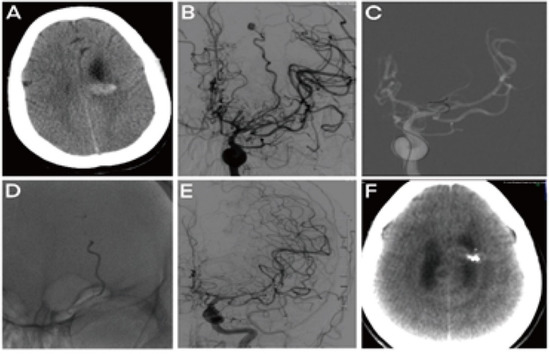

In this study, Type I aneurysms (17, 77.3%) were wholly embolized in all patients, and the AVM nidus in four was partially occluded, with two choosing follow-up and two undergoing microsurgical resection. Two patients developed intra-operative hemorrhages during microcatheter super-selection; one had intraoperative thrombosis with effective handling. Four of the five Type IIb patients had complete occlusions of the aneurysm; however, the pericallosal artery branch aneurysm remained visible after the partial occlusion in one patient. One Type IIb patient had a curative occlusion of AVM, two had partial occlusions for further follow-up, and the other two patients had partial occlusions of the main supplying arteries for further surgical resection. No operation related complications occurred. According to our experience, the application of an Apollo detachable microcatheter is recommended for aneurysms that reside within three centimeters of an AVM nidus. During the procedure, the tip of the detachable microcatheter should be positioned close to the nidus with the detachment point proximal to the aneurysm, allowing the gel reflux to aneurysmal sacs to occlude the aneurysms and nidus together (Figure 2). If two microcatheters could be accommodated within the parent artery simultaneously, detachable microcatheters are recommended for injecting the LEA after aneurysm coiling via the other microcatheter. Furthermore, the use of detachable microcatheters could decrease the risk of catheter withdrawal. In addition, if the parent artery irrigates essential functional areas, it is critical to preserve the blood flow, manage accompanying aneurysms, and consider coiling or microsurgery [1].

Figure 2. AVM with peripheral hemorrhagic aneurysm. (A) Preoperative CT revealed hemorrhage in the corpus callosum’s ventricle and splenium (B) DSA demonstration of the splenium of the corpus callosum AVM supplied by the right posterior cerebral artery branches and the branches of the right anterior cerebral artery, accompanied by a blood flow related aneurysm. (C) Super selection and positioning of the microcatheter through the left vertebral artery, preparing for the embolization. (D) Embolization of the AVM and accompanied aneurysm with Onyx. (E) Arteriography after embolization revealing the complete embolization of the AVM and the aneurysm. (F) CT scan before discharge, revealing adequate treatment.